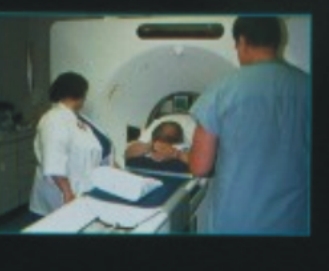

影像取得 |

定位及確定角度 |

所使用的治療方式是以三度空間的順形治療技術,即由電腦斷層或核磁共振影像,確定治療之標的物,且將影像輸入三度空間治療計劃系統,由此軟體之運算可決定最適合腫瘤形狀及大小之治療照野、治療角度及所需之治療附屬工具之使用機會,以幾近完美之劑量分佈涵蓋腫瘤所需治療之範圍。此外再搭配良好之體外固定系統(真空墊)以確定重覆治療之準確性。所有治療均可於門診實施。所使用腫瘤劑量為45~60葛雷(Gy),分次於5~6週進行(每天一次,每週五天)。